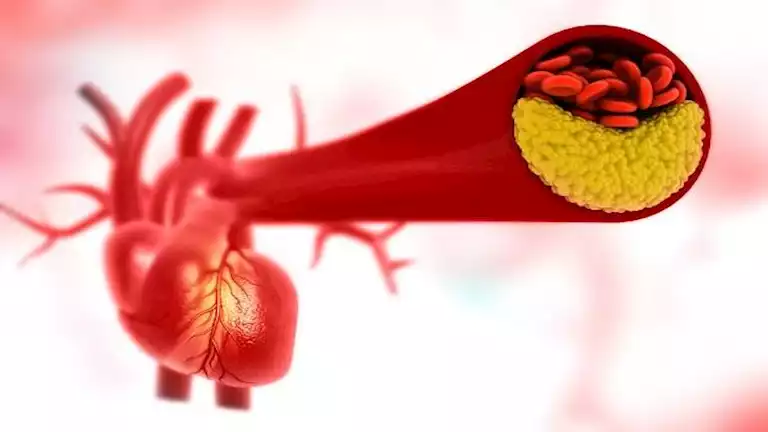

قد تشير علامة غير عادية على الجلد إلى انسداد الشرايين،بينما يشير الشكل الشبكي أحيانا إلى تلف الأنسجة أو أعضاء الجسم المهمة. وبالرغم من شيوع العلامات مثل...

أظهرت دراسة حديثة أجراها علماء في جامعة بون الألمانية أن تناول الشوفان ليومين فقط يمكن أن يقلل مستوى الكوليسترول الضار، يدعم عملية الأيض، ويساهم في تحسين...